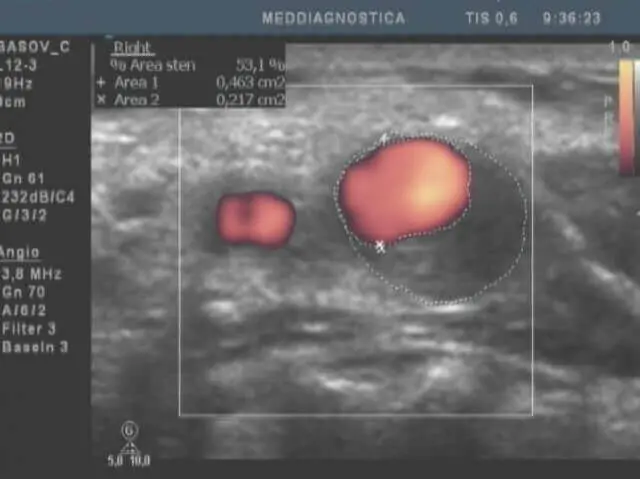

Нижче наведені приклади візуалізації атеросклеротичного ураження судин.

Найдоступніший спосіб діагностики і самий ефективний – це атеросклеротичний тест (розробка клініки «Меддіагностика»). Він дозволяє протягом декількох хвилин визначити наявність атеросклерозу і його стадію. Ми виявляємо наявність атеросклеротичних бляшок, визначаємо ступінь звуження судин серця, а також – найбільш ранні прояви атеросклерозу – потовщення внутрішнього шару судин. На цьому етапі ми можемо ефективно впливати на процеси розвитку атеросклерозу. Часто вдається стабілізувати процес або навіть зменшити його прояви.